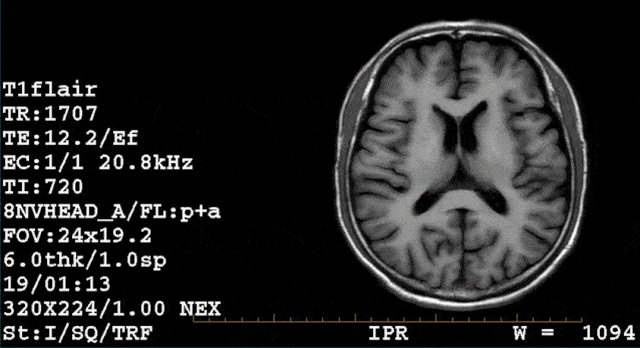

怎么看mri序列及信号 常用序列:t1wi t2wi pdwi

ir脉冲序列:flair flair用于t2wi和pdwi中抑制脑脊液的高信号,使